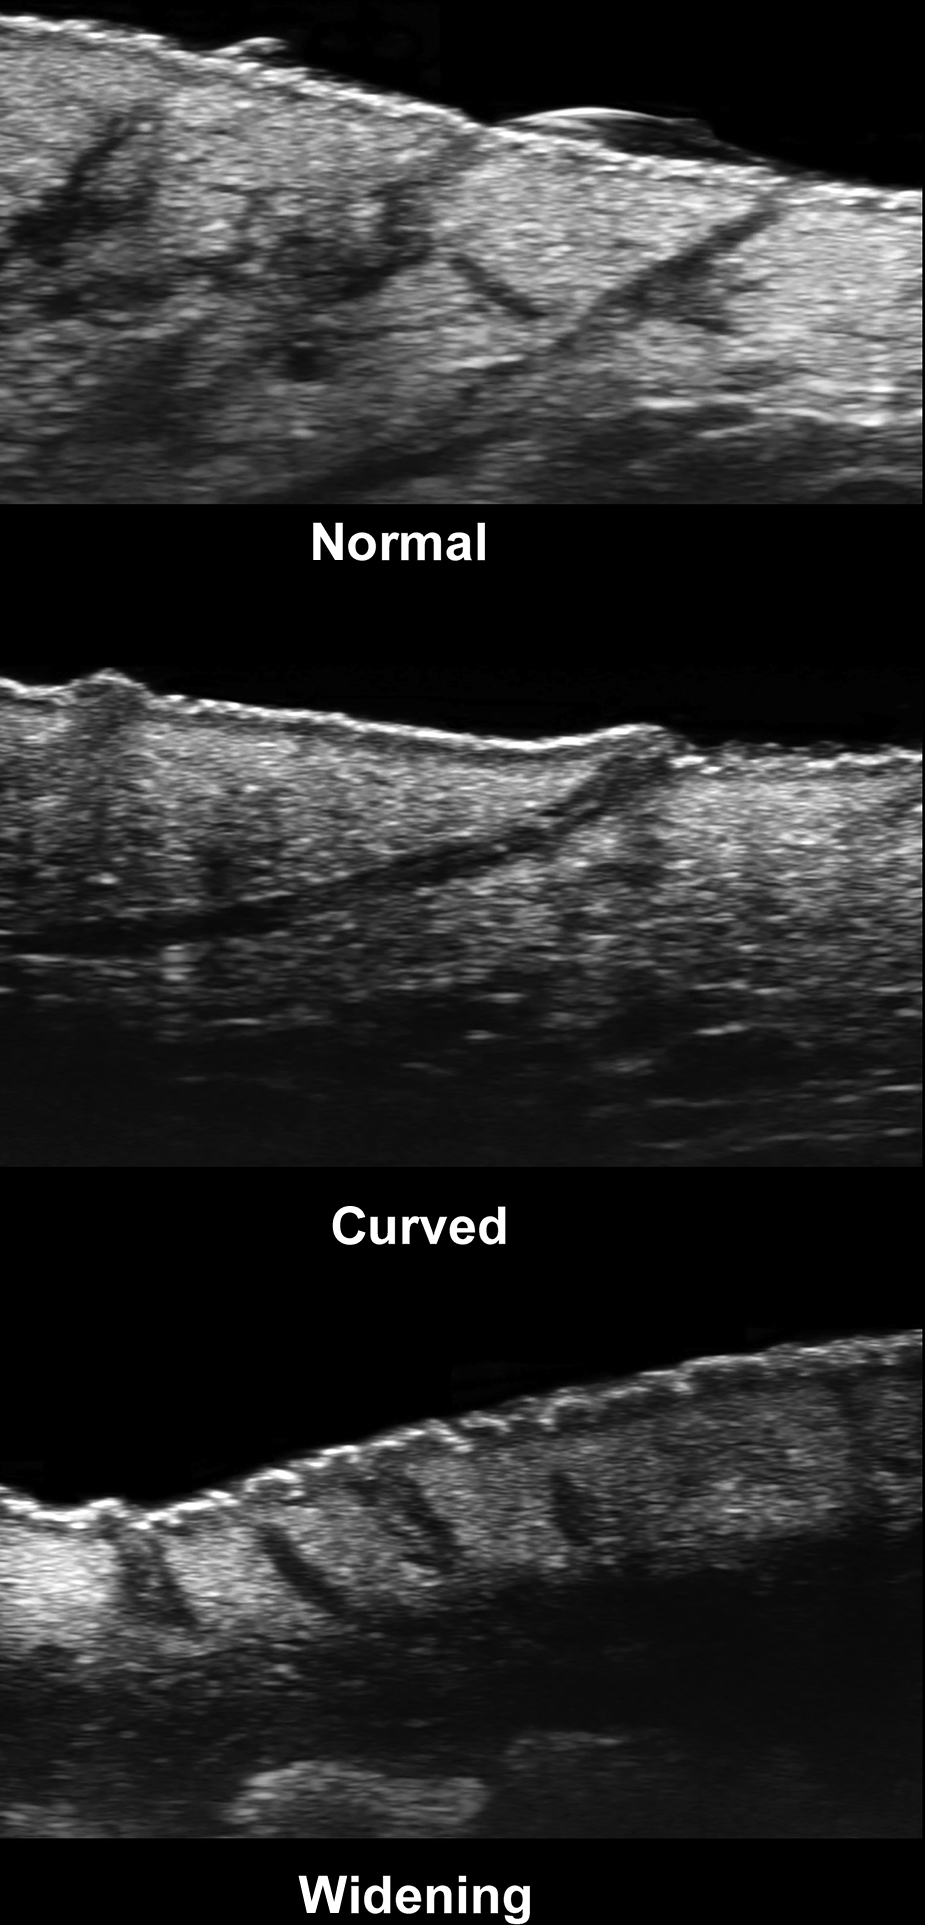

For detecting early subclinical and submillimetric abnormalities, it is necessary to have ultrasound devices that work with multifrequency probes that present their upper ranges ≥ 50 MHz, which may not be widely available. However, if these ultrasound machines are available, they will allow detection of the following early signs ( Figs. 6.3 to 6.5 ) :

- 1.

Modification of the axis of the hair follicle from straight (slightly oblique) to curved

- 2.

Thickening of the hair follicles and tracts

- 3.

Ballooning of the hair follicles

- 4.

Donor Sign: Dilated hair follicles that donate their keratinous content to fluid collections and tunnels.

- 5.

Sword Sign: Fragments of hair tracts going from the cavity of a dilated hair follicle to the surrounding dermis.

- 6.

Bridge Sign: Communications between adjacent and curved hair follicles. These connections may be conformed by single or multiple bridges between neighboring hair follicles.

- 7.

Two types of fragmentations of the keratin are multifragment and cylindrical. Multifragment is the presence of multiple small fragments of hyperechoic linear fragments within the dilated hair follicles, fluid collections, or tunnels. The cylindrical type is composed of hypoechoic thick bands within the same structures that sometimes may show hyperechoic borders.

The signs significantly associated with the disease’s severity are the presence of “bridge” and “sword” signs and the cylindrical type of keratin fragmentation. Thus, tunnels and fibrotic changes are more frequent in these cases. The rest of the ultrasonographic signs may explain the initial formation of the primary clinical lesions.